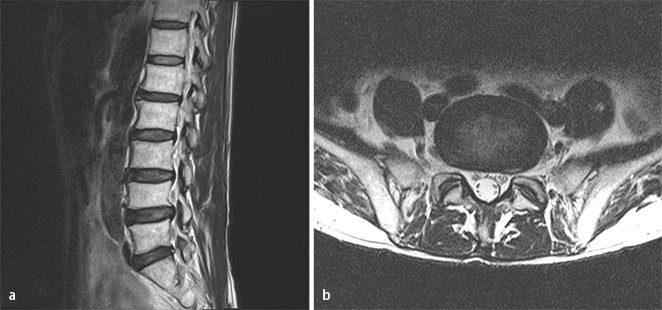

Degenerative Lumbalskoliose Wenn sich der bereits beschriebene Verschleiß in mehreren Wirbelelementen findet, kann es zu einer Verkrümmung der Wirbelsäule zur Seite hin (sog ‚Skoliose‘) kommen Normalerweise tritt eine Skoliose im Alter zwischen 10 und 12 auf. Die weitaus häufigsten degenerativen Beschwerden der Wirbelsäule finden sich im Lendenwirbelsäule (LWS) Bandscheibenvorfälle Bei Bandscheibenvorfällen (Abb 4a und 4b, MRT bei Bandscheibenvorfall LWK 3/4 rechts) wird zumeist über einen dorsalen Zugang eine mikrochirurgische Operation vorgenommen (Mikrodiscektomie). Im Laufe des Lebens kann es anlagebedingt, sowie durch allgemeinen Verschleiß zu Veränderungen der anatomischen Charakterzüge kommen, so dass die funktionellen Eigenschaften der Wirbelsäule beeinträchtigt werden Diese Veränderungen werden als degenerative Veränderungen bezeichnet.

Unter der Krankheitsbezeichnung Spondylarthrose versteht man die degenerative Veränderung der Wirbelsäule Synonyme Bezeichnungen sind Wirbelgelenkarthrose, Facettensyndrom oder Facettengelenkarthrose Diese chronisch degenerative Erkrankung der Wirbelgelenke (Facettengelenke) tritt am häufigsten im Bereich der Lendenwirbelsäule auf. Mit einer ausgeprägten degenerativen Veränderung bezeichnet man einen starken Rückgang von Gewebe An der Wirbelsäule können damit ein starker Rückgang von Bandscheibengewebe oder starke Veränderungen an den Wirbelknochen gemeint sein Dieser medizinische Begriff wurde für Sie übersetzt von. Rückenschmerzen sind in zunehmendem Alter oft auf degenerative Veränderungen der Wirbelsäule zurückzuführen Davon sind einerseits die Bandscheibe, andererseits häufig auch die kleinen Wirbelgelenke betroffen Während Symptome degenerativer Veränderungen im Anfangsstadium in der Regel durch Physiotherapie effektiv gelindert werden.

Unter der Krankheitsbezeichnung Spondylarthrose versteht man die degenerative Veränderung der Wirbelsäule Synonyme Bezeichnungen sind Wirbelgelenkarthrose, Facettensyndrom oder Facettengelenkarthrose Diese chronisch degenerative Erkrankung der Wirbelgelenke (Facettengelenke) tritt am häufigsten im Bereich der Lendenwirbelsäule auf Die. Degenerative Veränderungen an der Wirbelsäule treten individuell unterschiedlich mit voranschreitendem Lebensalter auf Einerseits hängt dies von äußeren Faktoren, wie z B jahrelanger schwerer körperlicher Tätigkeit ab, kann aber auch genetisch beeinflusst sein, wie neuere Untersuchungen zeigen konnten. Degenerative Veränderungen der Wirbelsäule ICD10 Diagnose M479 Diagnose Degenerative Veränderungen der Wirbelsäule ICD10Code M479 Der ICD10 ist eine internationale Klassifikation von Diagnosen ICD10SGBV (die deutsche Fassung) wird in Deutschland als Schlüssel zur Angabe von Diagnosen, vor allem zur Abrechnung mit den Krankenkassen.